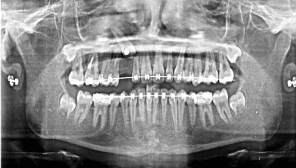

0.022 slot Roth brackets had been bonded on all upper and lower teeth except #12 which acted as a free body initially till the canine had been moved away from its root (Figure 3). After 6 months of alignment, space started to be created for the canine using opening coil spring (0.010 x 0.035 inch) (Figure 4). The first stage of surgery was planned to be VISTA technique in order to move the canine horizontally and to situate the canine crown directly under its socket using the microimplant (MI) (Figures 5 and 6). During surgery, all the bone distal to the canine crown till its CEJ which is in the way of its movement had been removed. A microimplant from (Ormco) VectorTas of 2 x 8 mm had been placed in the infrazygomatic crest parallel to the upper right first molar (Figure 7). A lingual button bonded on the labial surface of the canine and connected to the microimplant via a power chain which was passing under the alveolar mucosa over the canine. The horizontal movement of the crown had been activated every month by cutting a hole from the power chain. A panoramic periapical radiograph A-B taken directly after MI placement and 3 months over that to control the movement of the canine (Figures 8 and 9). After 3 months of horizontal movement of the canine, the patient referred again for the 2nd stage of surgery where a full reflected flap performed in order to remove the old power chain and place new one which is directly connected to the main archwire (Figure 10). All the bone above the canine crown till the 2 mm from the alveolar crest had been removed in order to facilitate the tooth movement vertically. The main arch wire which is 0.017x0.025 Stst had been offset in the area between #12, 14 (Figure 11). This offset placed to help for keeping the canine root in the alveolar bone and avoid the labial tipping of the crown. A crimpable attachment with a hook fixed on the wire directly over the canine crown and a power chain connected directly from the lingual button to the hook (Figure 12). The vertical movement of the crown had been activated every month by cutting a hole from the power chain. After the canine came out of the soft tissue a bracket bonded and thin wire placed in its slot with a sequence of 0.12 Niti, 0.14 Niti, 0.16 Niti, 0.16 x 0.22 Niti, 0.16 x 0.22 Stst, 0.17 x 0.25 Niti and 0.17 x 0.25 Stst. Canine root torque had been checked after its reaching to the occlusal plane and found that no need for any adjustment since it is similar with the opposing canine root eminence (Figure 13). After 24 months of active treatment, all appliances were debonded (Figure 14). Orthopantogram, lateral cephalography and periapical radiograph had been taken to record as a baseline for future follow up and assessment. Clear overlays delivered for both arches as retainers with proper instructions (Figure 15).

Figure 15. Panoramic, lateral cephalometric and peri apical radiographs after orthodontic treatment finished